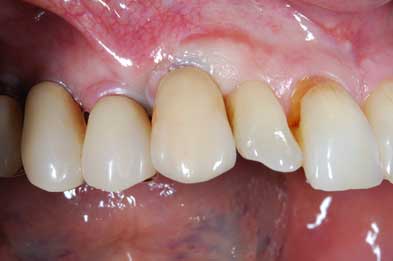

Impianto post-estrattivo

In un paziente cardiopatico di 72 anni